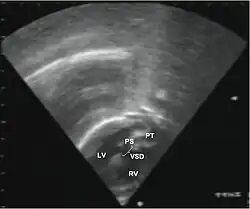

- Echocardiogram: An echocardiogram is an ultrasound of the heart that accurately assesses the heart’s structure and function, and can show the specific features of TGA, if present. This imaging modality allows for the definitive diagnosis of TGA to be made.[3]

Abbreviations: LV and RV=left and right ventricle, PT=pulmonary trunk, VSD=ventricular septal defect, PS=pulmonary stenosis.